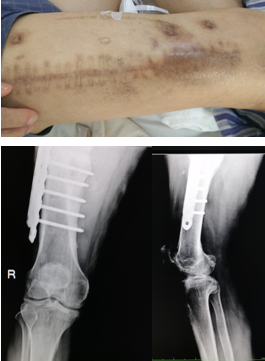

术前:

术后:

患者安徽淮安居民,于2019年4月份右下肢出现红肿,在当地医院,予以保守治疗,稍好转,患者为进一步治疗,来我院就诊。

患者入院后,完善相关检验检查,曾晓峰主任及其管床医生明确诊断,制定手术方案,于2019年07月05日行骨髓炎清创取骨植骨术,2小时55分的手术顺利,术后予以对症治疗,患者伤口愈合可,未见明显红肿。